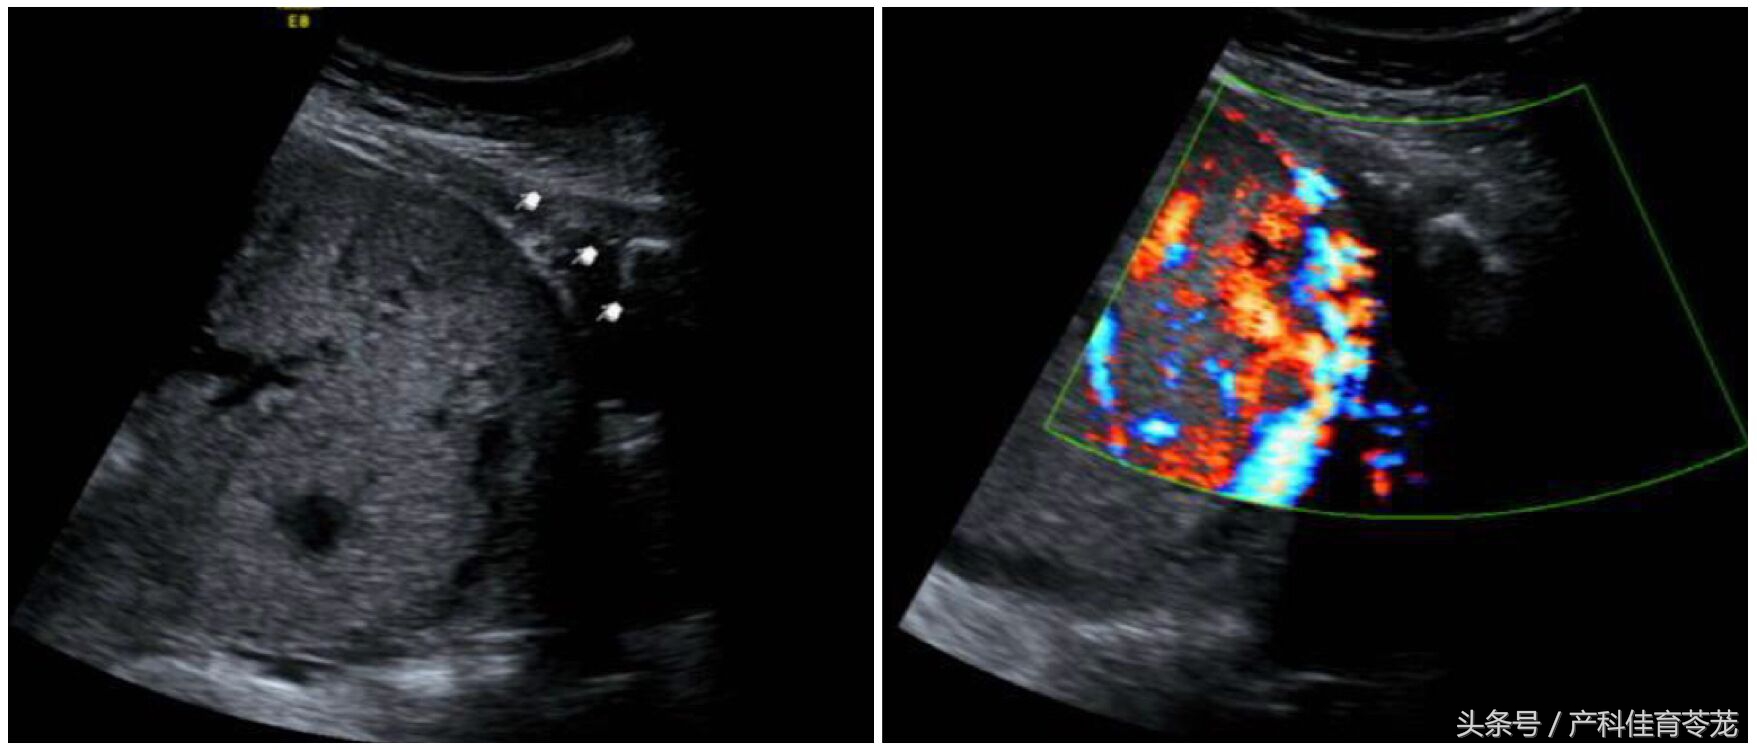

她是因为孕囊种植于瘢痕处,继续妊娠至孕中期,发展成了胎盘长在瘢痕处,并且进了子宫肌肉层,专业术语为”胎盘植入“,就是这样:

下图是胎盘植入: